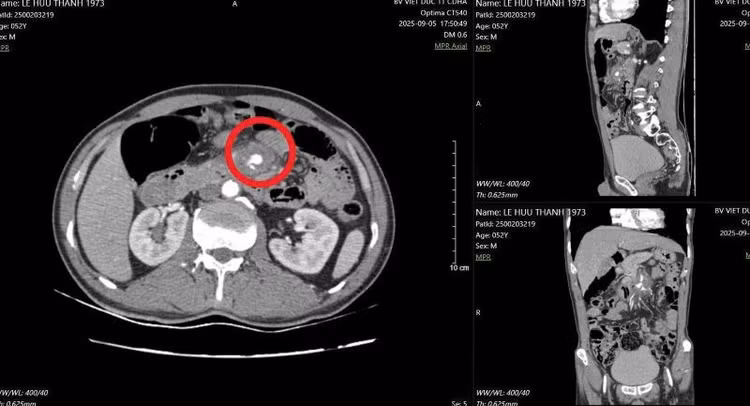

Hình ảnh đoạn D3 tá tràng tổn thương, cạnh động mạch mạc treo tràng trên - Ảnh BVCC

Nguy hiểm hơn, đầu tăm tiếp tục đâm vào một trong những mạch máu lớn nhất trong ổ bụng – động mạch mạc treo tràng trên, là nơi đưa máu nuôi phần lớn ruột non. Tổn thương này đã khiến thành mạch máu bị phồng lên giả tạo (gọi là “giả phình mạch”), nếu không được phát hiện và xử trí kịp thời có thể gây vỡ mạch, chảy máu ồ ạt trong ổ bụng, đe dọa tính mạng.

Đây là tình huống hiếm gặp nhưng vô cùng nguy hiểm, đe dọa trực tiếp đến tính mạng người bệnh nếu không được cấp cứu kịp thời. Đồng thời việc xử trí tổn thương đường tiêu hóa kết hợp với mạch máu cũng hết sức phức tạp.